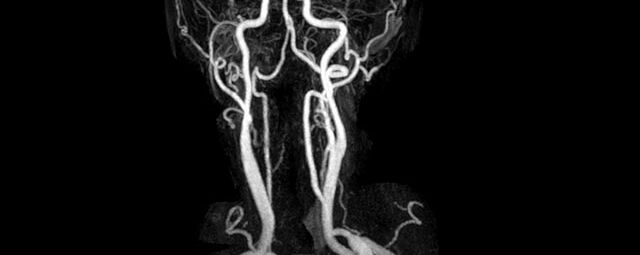

• Halsgefäße zur Therapieplanung (z.B. Stent, Operation)

• Bauchgefäße

• Erfassung und Verlaufskontrolle bei arteriellen Aneurysmen (Aussackungen der Arterien), vor allem der Bauchaorta

• Darstellung von Gefäßengen an Nierenarterien, Baucharterien und Becken-/Beinarterien

MR-Angiografie (MRA)

• MR-Angiographie mit Kontrastmittel

• Erfassung arterieller und venöser Gefäße/Bypässe aller Körperregionen mit 3D-Rekonstruktion